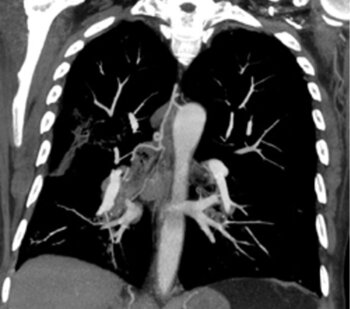

CT des Thorax (coronare MPR): Typisch gewundener Verlauf der kräftigen rechten Bronchialarterie, die den Lungentumor versorgt. (MPR=MultiPlanare Reformation)